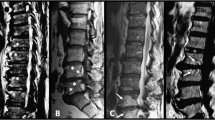

Our radiographic results of the ank/ank mice were comparable to those from previous reports [6]. We focused mainly on structural changes, in both the peripheral joints and the spine. The 8-week-old ank/ank mice showed increased mineralization in the distal interphalangeal joints (Figure 1B; white arrows). From 12 to 18 weeks, joint calcification became more pronounced progressively and extended to more proximal joints (Figure 1D and 1E; white arrows). The differences in the axial skeleton were subtle at 8 weeks, with early syndesmophytes at the vertebral corners of ank/ank mice (Figure 2B; red arrows). By 12 weeks, the corner syndesmophytes were well formed in the ank/ank vertebra (Figure 2D; red arrows), which progressed to syndesmophytes by 18 weeks (Figure 2E; red arrows).

Radiographs of spines from wild-type versus ank/ank mice. Eight-week-old mice appear in (A) and (B); 12-week-old mice in (C) and (D); and 18-week-old mice in (E) and (F). Red arrows in (B) show spurs between the vertebral bodies of 8-week-old ank/ank mice. Red arrows in (D) show early syndesmophytes at the edges of the vertebra from 12-week-old ank/ank mice. Red arrows in (F) show extensive marginal syndesmophyte formation between vertebral bodies from 18-week-old ank/ank mice.

The histomorphology of the vertebral column was significantly altered in 8-week-old ank/ank mice. Calcium apatite crystals were observed at the edges of the vertebral bodies (Figure 5B, thick arrow). Hypertrophic chondrocyte-like cells were replacing the annulus fibrosus (AF) and extending into the intervertebral disc (IVD; Figure 5B, thin arrow). Spinal sections of 12-week-old ank/ank mice showed a large amount of crystal deposition (Figure 5C, thin arrow) and early syndesmophyte formation (Figure 5C, thick arrow). The vertebral column of an 18-week-old ank/ank mouse showed ankylosis with fibrous connective tissue adjacent to some incomplete bony bridging (Figure 5D, thick arrow). The intervertebral disc at this stage was essentially replaced by a cellular proliferation composed of fibroblasts and large chondrocytic cells (Figure 5D, thin arrow). Higher magnification of the spinal sections showed that in wild-type mice, a few osteoblasts line the subchondral bone (Figure 6A, solid arrows). In 8-week ank/ank spine, the osteoblasts are more prominent and organized (Figure 6B, solid arrows), and calcific deposits (Figure 6B, dashed arrow) are present. In 12-week ank/ank spine, new bone formation (syndesmophyte, SYN; Figure 6C) developed where calcific deposits were located in younger mice. Numerous osteoblasts (solid arrows, Figure 6C) lined the new bone that was formed. Osteocytes are found embedded in the syndesmophyte (short dashed arrows; Figure 6C). In some ank/ank (18 weeks) spinal sections, large fusion masses of fibrocartilaginous tissues extend from one vertebra to the next, at the edges of the annulus fibrosus of the IVD (Figure 7). Within the fusion masses, "bone islands" appear, complete with bone marrow. These regions demonstrate the classic appearance of the growth plate, such as tidemark areas and organized subchondral layers (Figure 7, arrow).

Histologic examination of representative spine joints from wild-type versus ank/ank mice. (A) Vertebra from an 8-week-old wild type mouse. V, EC, AF, and IVD denote vertebra, endplate cartilage, annulus fibrosus, and intervertebral disc, respectively. (B) Vertebra from an 8-week-old ank/ank mouse. Thick arrow shows calcium apatite crystals at the edge of the vertebral bodies. Thin arrow shows hypertrophic chondrocyte-like cells replacing the annulus fibrosus and extending into the intervertebral disc. (C) Vertebra from a 12-wk-old ank/ank mouse. Thin arrow shows a large amount of crystal deposits. Thick arrow shows early syndesmophyte formation at the edge of the vertebral bodies. (D) Vertebra from an 18-week-old ank/ank mouse. Thick arrow shows ankylosis with fibrous connective tissue adjacent to some incomplete bony bridging. Thin arrow shows the intervertebral disc at this stage, and it was replaced by proliferative fibroblasts and large chondrocytic cells.